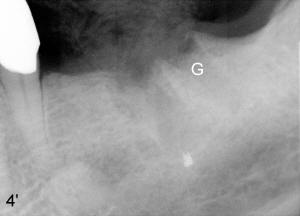

Mr. Lip returns to clinic for #30 and 31 implant placement. At the time of impression, there is no sign of gingival swelling around the tooth #19 (Fig.1: >; although the tooth has suspected root fracture). The patient requests keeping this affected tooth as long as possible while #30,31 implants are being placed and restored. This is not the case at the appointment of implant placement on the other side (Fig.1': *). There is localized gingival erythema and edema at the ML line angle. It appears that the treatment plan should be changed: the number of implants to be placed should be reduced from two to one and the infected tooth should be extracted to decrease the chance of implant infection. These two procedures are intended to be done at the same time so that bone harvested from #30 implant osteotomy (Fig.2) can be saved (Fig.2': < in dapen dish) and grafted in #19 sockets (Fig.3', 4'), particularly in the mesial one with severe bone loss due to root fracture.

Unfortunately, there is bone resorption around the implant 3 months postop (Fig.6: >, as compared to Fig.4). Granulation tissue is present over the implant (Fig.7 *). The patient complains occasional pain and swelling after implant placement. Bone resorption is confirmed after removal of granulation tissue around the implant (Fig.8 *). After acid etch, Endogain (Fig.9 *, Straumann) is placed around the implant (P: healing plug). Flaps are approximated with 4-0 plain gut suture. Collagen membrane should have been used. Amoxicillin is prescribed, but the patient does not take it. It appears that bone graft to the sockets of #19 helps form an apparently continuous bone plate at the alveolar crest over the mesial (M in Fig.6') and distal (D) sockets, as compared to Fig.4'.